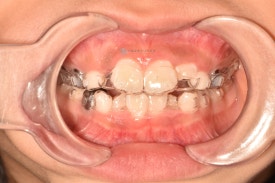

투명교정장치의 장점을 고려하여 어린이교정을 투명교정장치로 시작하였습니다. 아이의 협조도가 매우 좋아 하루가 다르게 예뻐져서 오네요!

기존 교정장치와 같은 철사 찔림이 없고 확장과 치아배열이 동시에 잘되는 투명교정장치입니다. 착용한 상태에서도 거의 티나지 않아 아이들이 좋아합니다.😁

치료 전 - 위아래 심한 공간 부족이 관찰됩니다.기존 교정장치와 같은 철사 찔림이 없고 확장과 치아배열이 동시에 잘되는 투명교정장치입니다. 착용한 상태에서도 거의 티나지 않아 아이들이 좋아합니다.😁